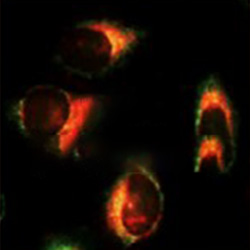

미토콘드리아

골지체

소포체#세포 품질 변별력의 독창성

#선별된 줄기세포 기능의 우수성

#세포 활용의 편의성

줄기세포 품질 관리 기술을 도입해 높은 퀄리티의 세포를 치료에 이용합니다.

줄기세포 치료의 효능을 높이기위해 철저한 관리를 진행합니다.